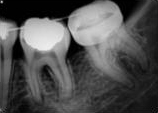

antes depois